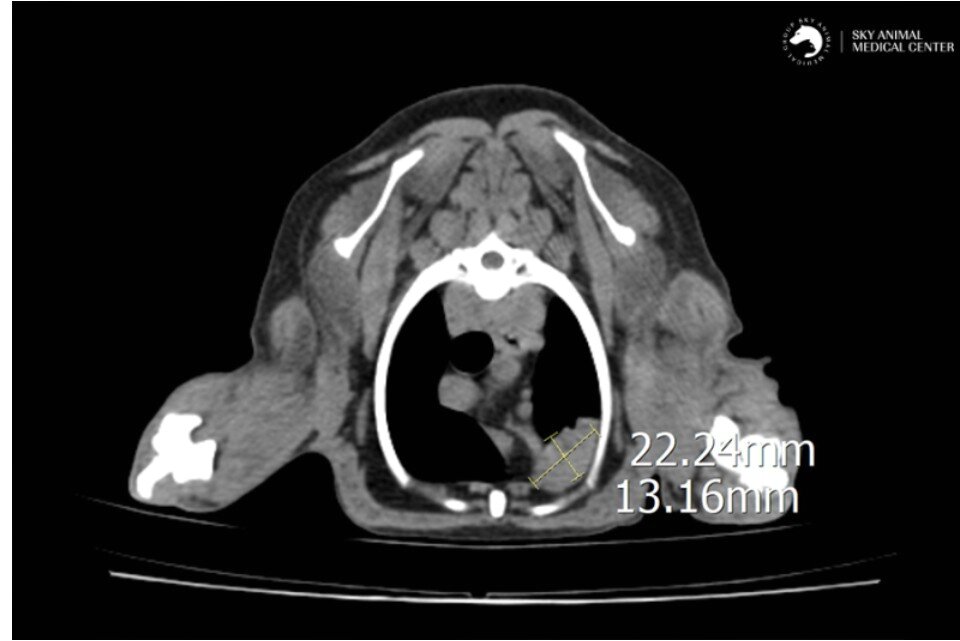

본문 이미지 - 바람이는 CT검사 결과 폐 좌측 전엽에서 종양이 의심되는 소견이 발견됐다(동물병원 제공). ⓒ 뉴스1

바람이는 CT검사 결과 폐 좌측 전엽에서 종양이 의심되는 소견이 발견됐다(동물병원 제공). ⓒ 뉴스1